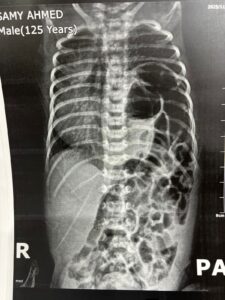

نجح فريق طبي بمستشفى الفيوم العام في إجراء جراحة دقيقة ونادرة لإنقاذ حياة رضيع يبلغ من العمر 9 أيام، كان يعاني من فتق خلقي بالحجاب الحاجز (Congenital Diaphragmatic Hernia – CDH)، وهي من الحالات الحرجة التي تتطلب تدخلًا جراحيًا عالي الدقة ورعاية طبية متكاملة.

وتُعد جراحات الفتق الخلقي بالحجاب الحاجز من أكثر العمليات تعقيدًا، نظرًا لحساسيتها واحتياجها إلى مهارة عالية في التعامل مع الحالة قبل وأثناء وبعد الجراحة، وهو ما يعكس مستوى الكفاءة والخبرة التي يتمتع بها الفريق الطبي بمستشفى الفيوم العام.